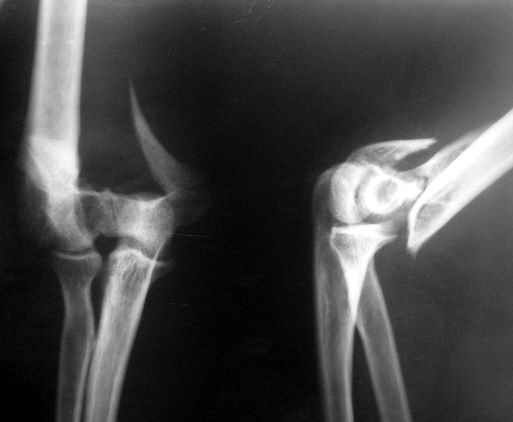

Obviously there is no elbow joint...the options are few: (from the worst to the "best"...if any)

3. Total elbow replacement (semi constrained - as no ligaments to stabilize the joint) - Coonrad-Morrey, Discovery - Biomet - considering his age there is limited indication for that procedure.

4. There is limited experience with total elbow allograft replacement with some rate of successes on one hand and high rate of complications on the

other hand. I personally would try this option as it is a reversible procedure and one could in a case of failure to replace it with prosthesis